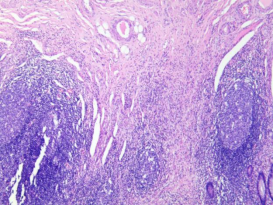

慢性阑尾炎

多由急性或亚急性阑尾炎发展而来,亦可一开始就是慢性炎,主要病变为阑尾各层不同程度纤维化和淋巴细胞、浆细胞浸润。

黏膜固有层大量浆细胞及淋巴细胞,

纤维组织增生